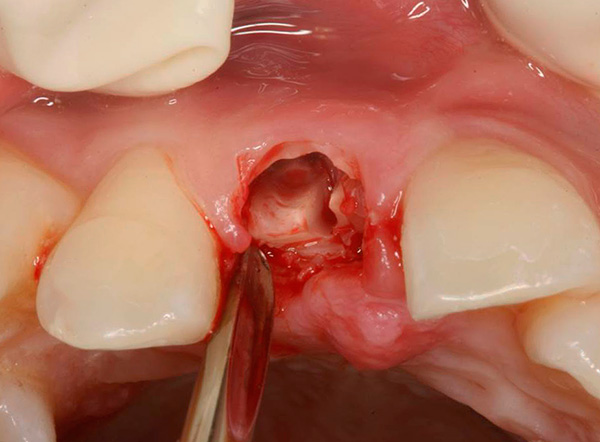

La seconda fase prevede l'inizio dell'operazione stessa: creare l'accesso all'apice della radice attraverso l'incisione della gomma, staccare i tessuti molli, ritagliare una piccola “finestra” speciale nell'osso e rilevare la radice del problema.

Al terzo stadio, una parte della radice con una cisti o un granuloma viene tagliata con un trapano, dopo di che vengono inseriti preparati nella ferita per stimolare la crescita ossea e accelerare la guarigione. La ferita è suturata.La nomina di farmaci per il trattamento domiciliare (inclusi gli antidolorifici) consente di ridurre al minimo le possibili sensazioni dolorose e consente al paziente di tornare alla normale vita in pochi giorni.

Le fotografie seguenti mostrano l'estrazione del dente, la cui parte della corona viene distrutta quasi al livello delle gengive:

Foto di un dente le cui radici sono separate da un trapano prima della rimozione: